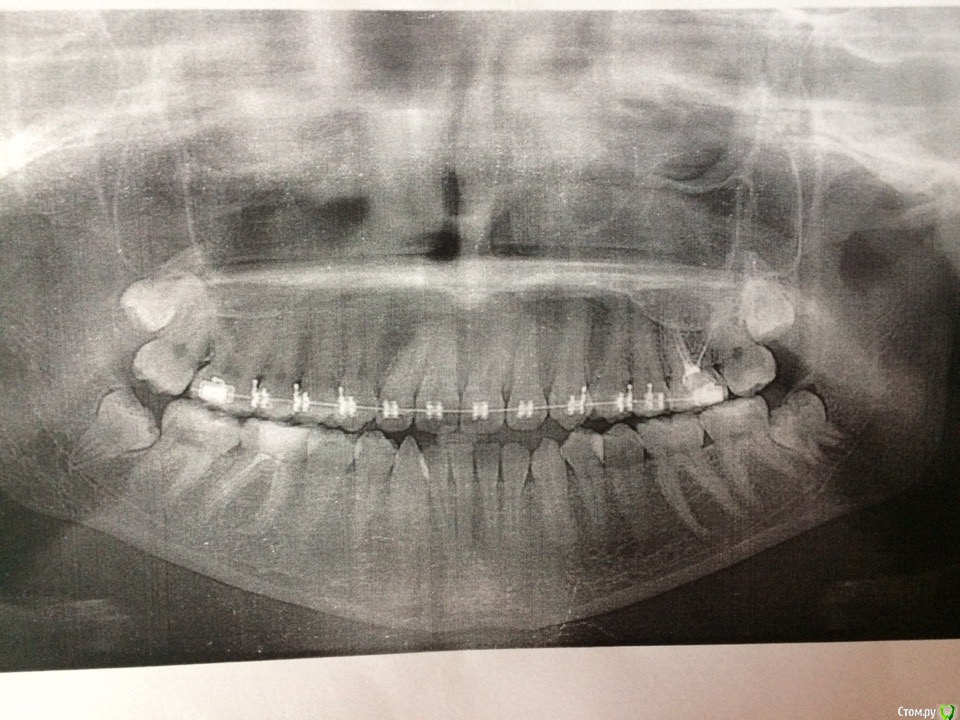

Здравствуйте! Вначале думали удалять с доктором две четвёрки , но позже (после снимка)Ортодонт назначил удаление 37 и 46 зубов для улучшения прикуса. 46 без нервов, но при этом беспокоил т.к там были воспалительные процессы(видно на ОПГ), я понимаю почему его, но не понимаю почему мы удаляем 37,а не 36. Нет сейчас возможности ехать к нему в клинику, т.к нахожусь в другом городе, могу только в сентябре , но к тому времени я уже должна удалить 2 зуба и ставить брекеты. Подскажите, можно ли удалять два разных зуба(37 и 46) или нужно удалять пару 36 и 46? не останется ли после лечения брекетами больших промежутков?

На фото 46 находится слева, а 37 справа( фото перевернуто )